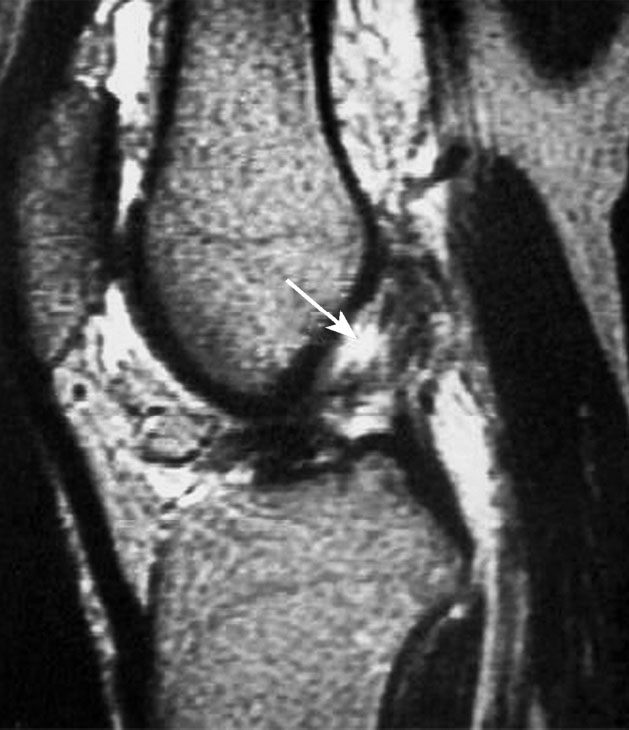

急性前交叉韧带损伤的磁共振成像表现

前交叉韧带损伤后出现的骨挫伤

前交叉韧带急性损伤最初的磁共振成像表现为T2像的髁间窝血肿,以及韧带纤维的不连续。另外,在股骨外髁和胫骨平台后方会出现骨挫伤,这种影像在前交叉韧带损伤中有很高的特异性。